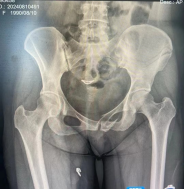

8月15日,颍上县人民医院骨科依托蚌埠医科大学第一附属医院紧密型医联体建设工作,通过专科针对化帮扶,由蚌埠医科大学主任医师吴敏教授开展手术带教与示范指导,成功开展骨盆骨折切开复位螺钉联合infix钉棒系统内固定术。

34岁的李梅(化名)因车祸受伤入院,我院将其影像数据及病情实时共享至蚌埠骨科专家团队,并在专家团队指导下完成了手术。